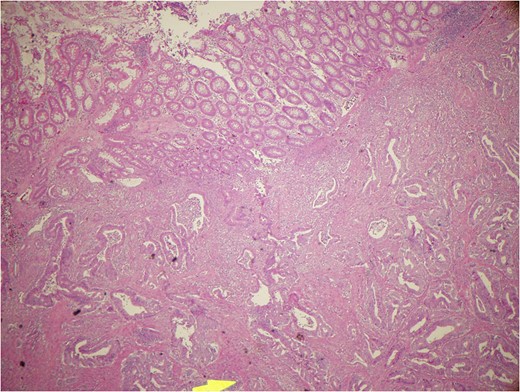

Gross examination of the ascending colon showed a fungating, friable, centrally ulcerated mass 3.5 cm from the distal surgical margin that is almost circumferential and 7.5 × 4.8 × 2.1 cm in greatest dimensions. Histopathologic examination revealed infiltrating well to moderately differentiated, mucous producing adenocarcinoma, extending through the muscle wall and microscopically into the pericolonic adipose tissue with metastasis to 1/34 regional lymph nodes (Fig.

9).

Figure 9:

Mucous producing adenocarcinoma.